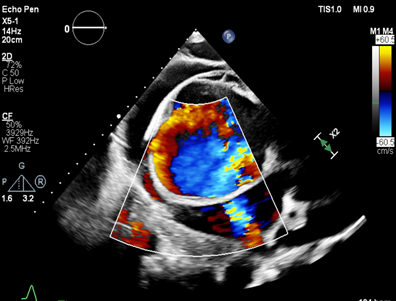

但危重肺动脉高压患者即使经过国际公认最佳联合治疗方案:安立生坦联合他达拉非或利奥西呱治疗后仍有很高的死亡率。研究证明心功能III-IV级患者1年生存率不到60%。危重肺动脉高压患者合并右心衰竭,重度扩张的右心压迫左心,导致左心输出量严重降低,机体重要脏器供氧不足。而指南所推荐的肺移植或心肺联合移植手术操作复杂,价格高昂,且受到供体来源的限制,在我国开展十分有限,远不能满足大量临床需求。如何破解这一困局?是否可以优化房间隔造口技术来挽救患者生命?

为攻克精准控制分流量的技术难题,荆志成教授带领团队采用“医工交叉”的创新研究策略。在对前期研究数据进行大量分析计算的基础上,制定了设定造口术后目标动脉血氧饱和度,计算目标分流量,再使用导管测定血流动力学参数和血氧含量数据,计算目标分流口径的策略,解决了如何精确计算患者所需要的房间隔造口的直径这一关键问题。随后,荆志成教授团队与武汉唯柯医疗科技有限公司紧密合作,设计了新型心房分流器实现精准控制分流量。同时设计了多种分流器孔径型号,且分流器设置偏心横向螺母端头,释放后可回收、可更换、可二次干预,只为用精心的设计确保经皮房间隔造口术为每一位患者带来最大获益。